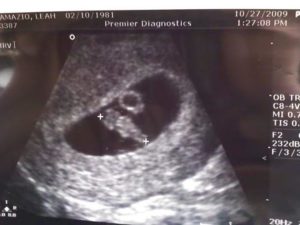

УЗИ

На УЗИ при 7 неделе беременности эмбрион выглядит как пшеничное зерно и имеет такие же размеры. Регистрация частоты сокращений сердечных мышц фиксирует учащение сердцебиения до 165 ударов в минуту. Врачи объясняют это переходом на очередной этап развития сердца.

Трудно поверить, что ребенок на 7 недели уже в 10 000 раз больше, чем во время зачатия, всего месяц назад. В этот период активно развивается головной мозг, при этом каждую минуту появляется по 100 новых нервных клеток. Отчетливо на УЗИ еще не видно плеч, рук, ног, локтевых костей, бедер, голеней и коленей, но уже начинается процесс их дифференцировки.

УЗИ на 7 неделе беременности

Ультразвуковое исследование обычно проводится еще в момент постановки женщины на учет, на 6 неделе беременности. Однако, если этого не было сделано на предыдущей неделе по какой-либо из причин, УЗИ женщине предложат пройти сейчас.

УЗИ на 7 неделе беременности уже четко выявляет и определяет плод в матке. И пусть пока еще определить его пол не представляется возможным, зато можно услышать и увидеть, как бьется сердечко малыша. Кроме того, с помощью УЗИ врач может уточнить длину эмбриона, а мама с папой – рассмотреть форму своего растущего не по дням, а по часам ребеночка.